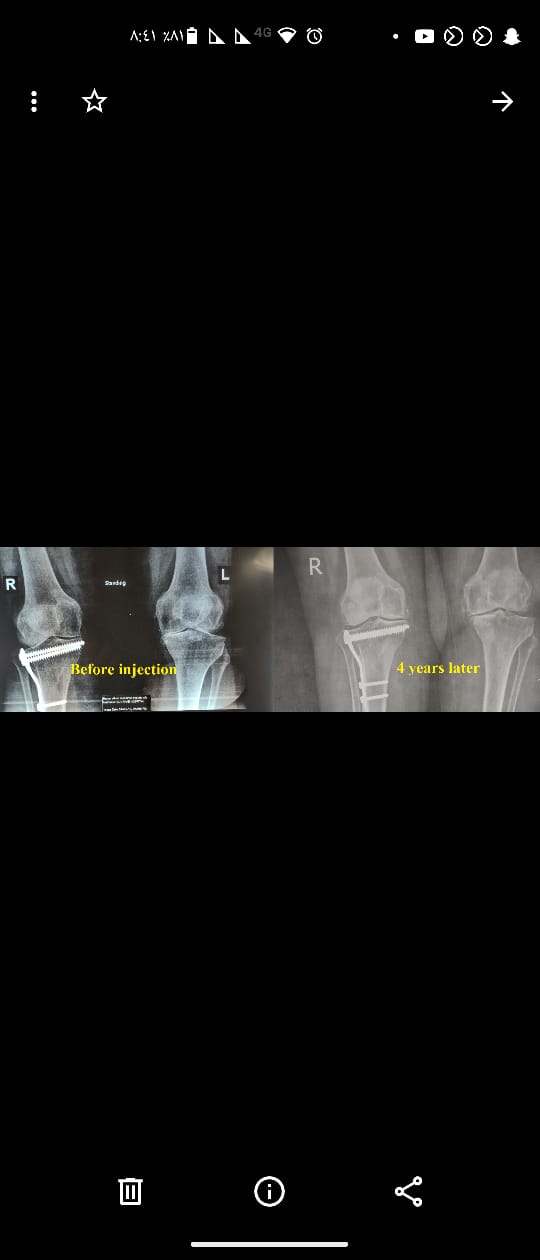

* لا، فقد تم ابتكار طريقة غير جراحية لعلاج حالات خشونة المفاصل الشديدة، وهو الحقن الخلوي الموضعي المحفز بالموجات الكهرومغناطيسية غير المؤينة، حيث سينتج عنه تلاشي الألم الناتج عن الخشونة تماماً أو تناقصه بنسبة تتراوح بين١٠-٥٠%، خلال الأيام الأربعة الأولى بعد الحقن وسيقل الألم المتبقي تدريجياً مع إعادة بناء للأجزاء المتآكلة في المفصل خلال سنة واحدة من الحقن.

(7): هل تأثير الحقن الخلوي الموضعي المحفز بالموجات الكهرومغناطيسية غير المؤينة مؤقت أم مستمر؟

* من الناحية النظرية التأثير مستمر لكن أقصى مدة متابعة فعلية كانت منذ عام ٢٠١٥، بمعنى أن التحسن الفعلي ممتد لما يزيد عن٩ سنوات.

(10): ما هي نتيجة الحقن الخلوي؟ وهل أثره مستمر؟

* تقوم الخلايا بعملية إعادة بناء الأجزاء المتآكلة نتيجة الخشونة وأثره مستمر في٨٠ % من الحالات.